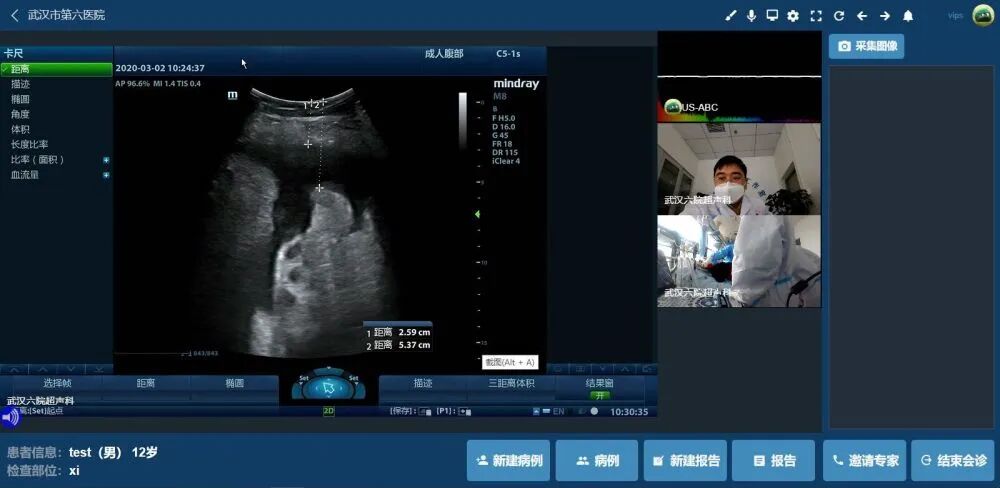

“抽到腹水啦!抽到腹水啦!”3月2日下午,从武汉市第六医院(江汉大学附属医院)ICU(重症医学科)病区传来成功的欢呼声,危重症新冠肺炎患者腹腔积液超声引导下穿刺成功,指导穿刺的超声影像科医生不在病区现场,而是通过手机云端平台完成了超声诊断及引导定位,这就是5G远程超声强大魅力所在。

据悉,5G超声云介入运行第一天,通过云端已为4位危重症新冠肺炎患者进行了胸腔、腹腔、肺部、心脏等脏器的检查诊疗,通过实时5G同步传输,线下即时操作、云端超声介入、远程专家会诊三者结合,为病人及时诊断赢得时间。

“同济大学附属上海第十人民医院为我院驰援提供的超声云设备,疫情当下,5G助力,实现了云端实时诊疗。同时,在云端,复旦大学附属中山医院超声专家为我院重症医学科完成了一例疑难心脏超声病案远程会诊,可谓一个云端牵起鄂、沪之情。”刘爱华主任对记者说。被电话问及远程会诊感受时,复旦大学附属中山医院超声科赵维鹏教授表示,“云端会诊和现场做彩超一样,现场感、便捷度都很好,心脏疑难彩超远程多专家会诊,可实时云端准确诊断,帮助临床一线医生进行下一步治疗方案的制定。”